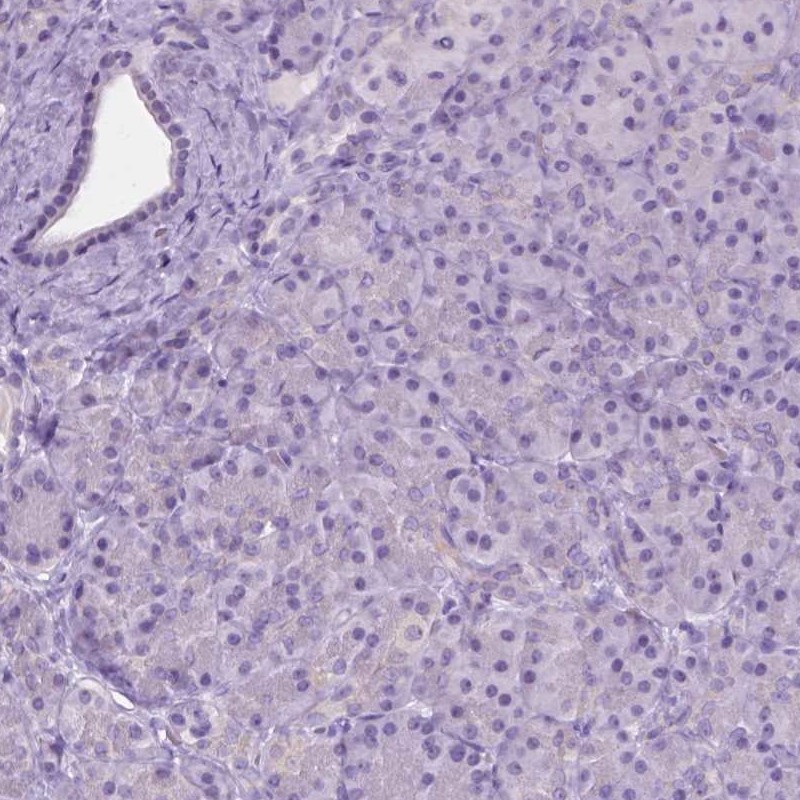

Immunohistochemistry analysis in human cerebral cortex and pancreas tissues using Anti-GPR37L1 antibody. Corresponding GPR37L1 RNA-seq data are presented for the same tissues.